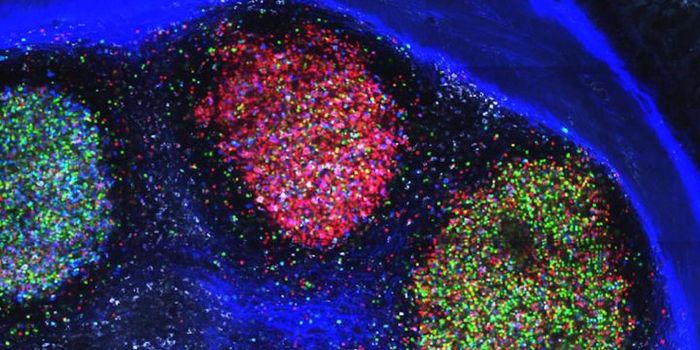

DEC 10, 2015ImmunologySuperior technology brings us novel images of cancer cells and lymphocytes this week, and now scientists can learn more ...